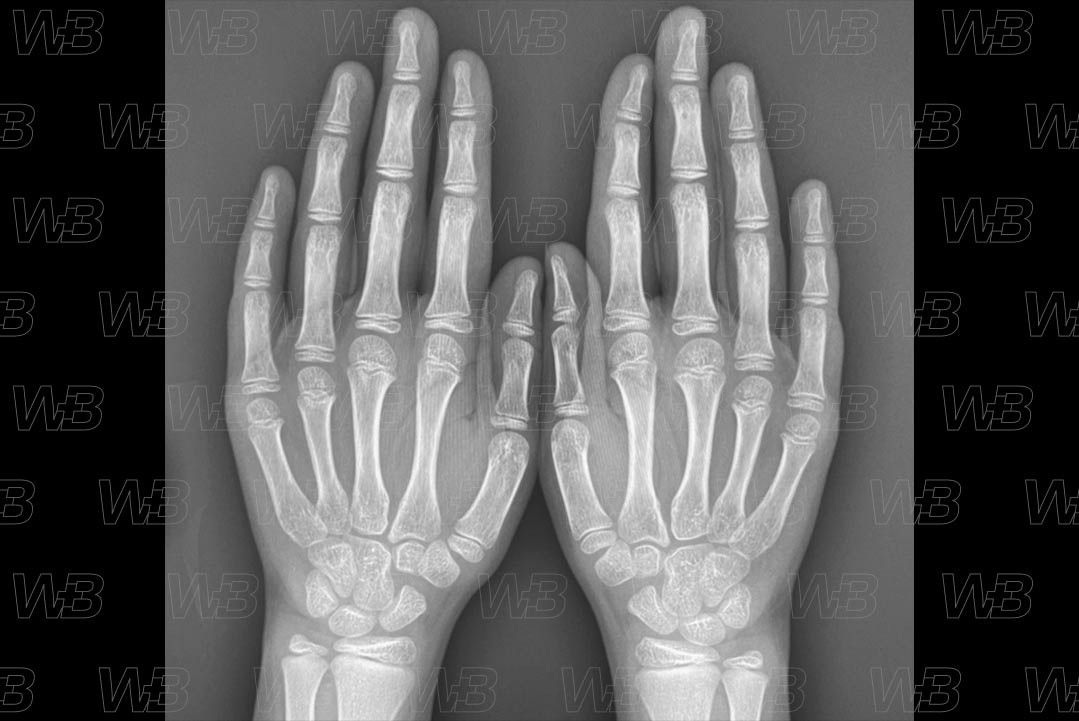

Atlas idade óssea - Feminino - 7 anos e 10 meses

RADIOGRAFIA MÃOS E PUNHOS (IDADE ÓSSEA)

Feminino

7 anos e 10 meses:

• Estilóide ulnar;

• Sobreposição do trapézio e trapezóide;

• Epífise proximal do polegar se estende medialmente ultrapassando a metáfise.